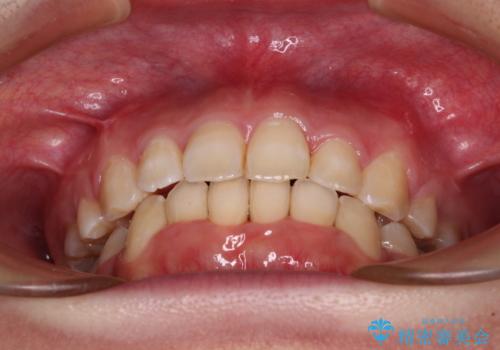

4本の歯を抜歯したことで、飛び出していた口元が引っ込み、横顔が大きく改善されました。

咬み合わせが悪化することのないようにスペースを閉じていくことができ、比較的スムーズに治療を進めることができました。